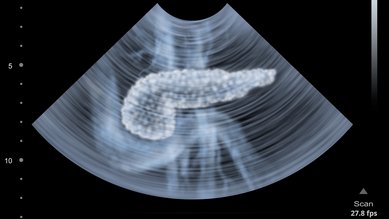

سرطان البنكرياس

يصاب حوالي 20,000 شخص في ألمانيا بسرطان البنكرياس كل عام. غالبًا لا يتم رصد الورم حتى وقتٍ متأخر. ونتيجةً لذلك، لا تكون فرص الشفاء جيدة.